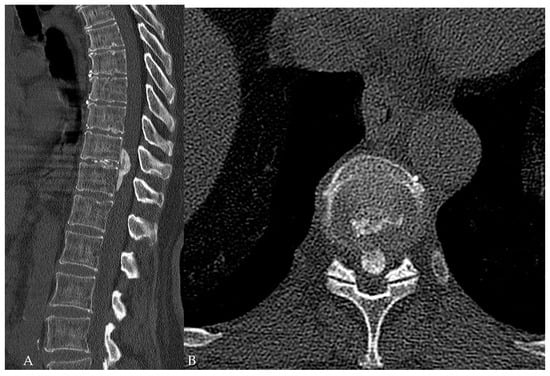

- Yuan, L.; Chen, Z.; Liu, Z.; Li, W.; Sun, C.; Liu, X. Clinical and radiographic features of adult calcified thoracic disc herniation: A retrospective analysis of 31 cases. Eur. Spine J. 2023, 32, 2387–2395. [Google Scholar] [CrossRef] [PubMed]